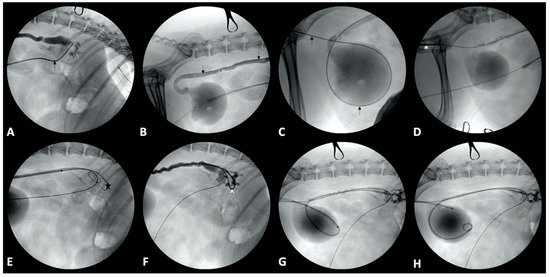

4.2. Urethra